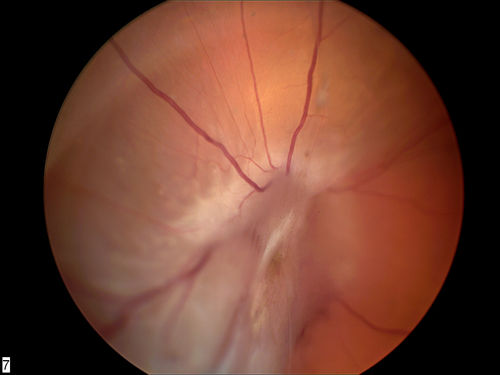

RD with PVR

RD with Proliferative Vitreoretinopathy